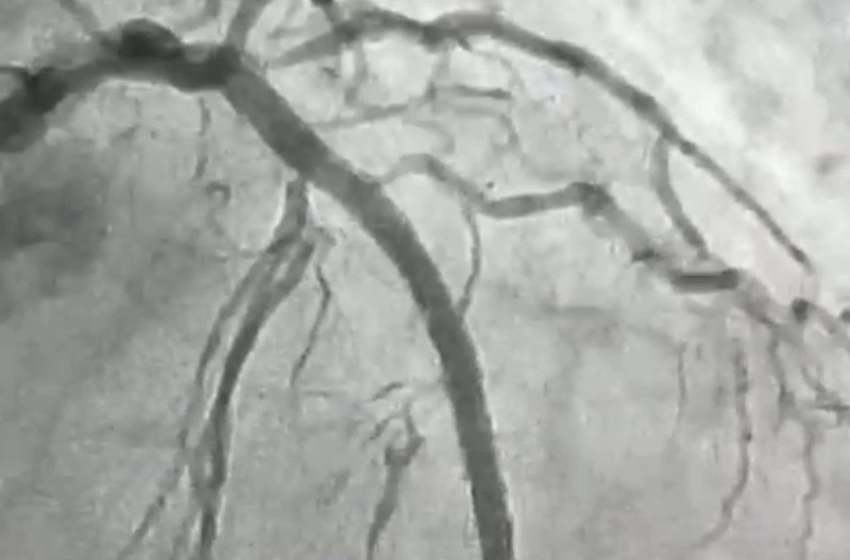

O procedimento foi realizado em uma paciente de 84 anos, moradora de Itaporanga, que apresentava uma lesão grave e altamente calcificada na artéria descendente anterior, considerada a principal artéria do coração. Segundo o cardiologista intervencionista, Jeann Santiago, um dos médicos responsáveis pela realização do procedimento, a condição exigia um tratamento extremamente delicado, com risco elevado, devido à dureza da placa obstrutiva, comparada pelos médicos a uma “pedra” no interior do vaso.

“Para possibilitar a abertura da artéria, a equipe utilizou a aterectomia rotacional, técnica que funciona como uma microfuradeira capaz de desgastar e desobstruir placas de cálcio muito rígidas. Em seguida, com o auxílio do ultrassom intravascular, foi possível medir com precisão a extensão da lesão e determinar o tamanho ideal dos dispositivos a serem implantados. Após a preparação do vaso, foram colocados dois stents farmacológicos, completando o processo de revascularização”, explicou o cardiologista.